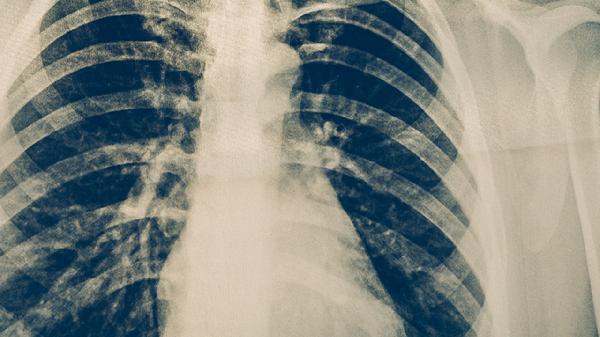

難治性肺結(jié)核可在醫(yī)生指導(dǎo)下使用中藥輔助治療,常用藥物包括百合固金片、抗癆顆粒、結(jié)核丸、補(bǔ)肺活血膠囊、百令膠囊等。中藥治療需結(jié)合規(guī)范抗結(jié)核西藥,不可替代標(biāo)準(zhǔn)化療方案。

中藥治療需在結(jié)核病??漆t(yī)師指導(dǎo)下進(jìn)行,嚴(yán)格配合異煙肼、利福平等一線抗結(jié)核藥物。治療期間應(yīng)保持高蛋白飲食,適量補(bǔ)充維生素A/D,避免勞累。每2個(gè)月需復(fù)查胸部CT及痰菌檢查,出現(xiàn)視力模糊、皮膚黃染等不良反應(yīng)時(shí)立即就醫(yī)。居住環(huán)境需保持通風(fēng)干燥,餐具單獨(dú)消毒,痰液需用含氯消毒劑處理。